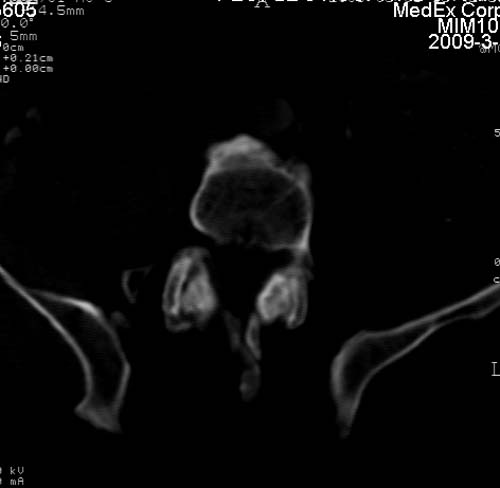

标题: CT18522:男,66岁。考虑结核有错吗 [打印本页]

标题: CT18522:男,66岁。考虑结核有错吗

x线片示:骶骨密度增高。

考虑----腰椎骶化-----退变-----椎管狭窄

腰骶椎退行性改变。

腰骶椎退行性改变,建议重建看看!

退行性变,椎体滑脱

腰椎滑脱并有退变

退行性变,椎体滑脱。建议同椎体平行进一步扫描。